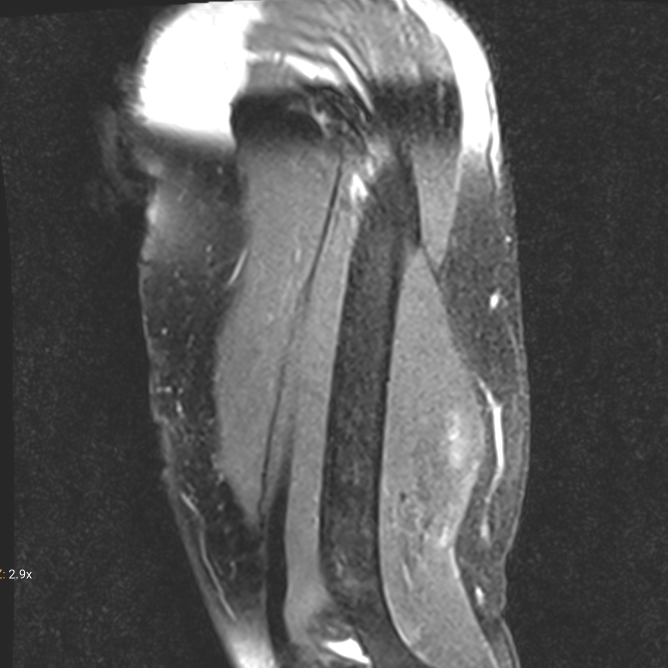

Der Tag rückt näher. Morgen ist es soweit. Nach etwa 20 Jahren zum zweiten mal. Das Schwannom nervus radialis im linken Oberarm wird operativ entfernt. Es ist